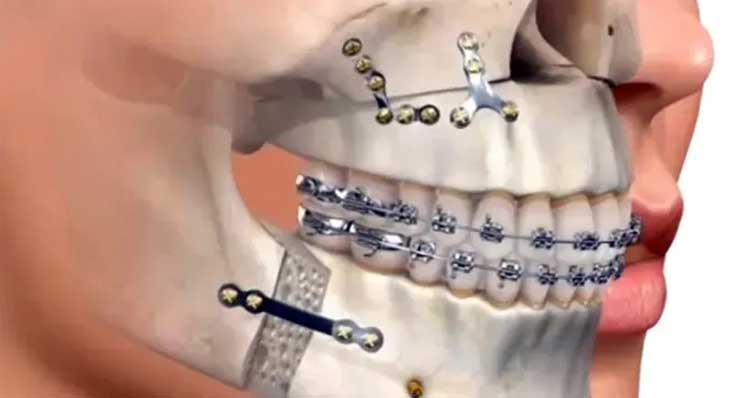

این مهم ترین مرحله است. متخصص ارتودنسی با استفاده از ارتودنسی ثابت، دندان ها را در هر فک به صورت مستقل صاف و مرتب می کند تا برای یک رابطه فکی جدید آماده شوند. - مرحله دوم: جراحی فک

پس از آماده شدن دندان ها، جراحی در بیمارستان و تحت بیهوشی کامل انجام می شود و جراح فک ها را در موقعیت جدید خود با پیچ های تیتانیومی ثابت می کند. - مرحله سوم: دوره نقاهت (چند هفته)

پس از بهبودی اولیه، متخصص ارتودنسی مرحله نهایی درمان را برای تنظیم دقیق بایت و دستیابی به شکل صحیح قرار گرفتن دندانها روی هم با استفاده از کش ارتودنسی آغاز می کند.

- حذف جبران های دندانی (Decompensation)

بدن به طور طبیعی سعی می کند ناهنجاری فک را با کج کردن دندان ها جبران کند. متخصص ارتودنسی باید این جبران ها را حذف کرده و دندان ها را در موقعیت صحیح خود نسبت به استخوان فک قرار دهد. - هماهنگ سازی قوس های دندانی

قوس های دندانی بالا و پایین باید به گونه ای مرتب شوند که پس از جراحی، مانند کلید و قفل کاملاً روی هم قرار گیرند و یک نرمال بایت ایجاد کنند.

- ارتودنسی ثابت

بریس ارتودنسی فلزی به دلیل استحکام و کنترل بالا، رایج ترین انتخاب برای کیس های جراحی است. - ارتودنسی سرامیکی و دیمون

گزینه های زیباتری مانند ارتودنسی سرامیکی یا سیستم های پیشرفته تری مانند ارتودنسی دیمون نیز می توانند در این درمان ها استفاده شوند.